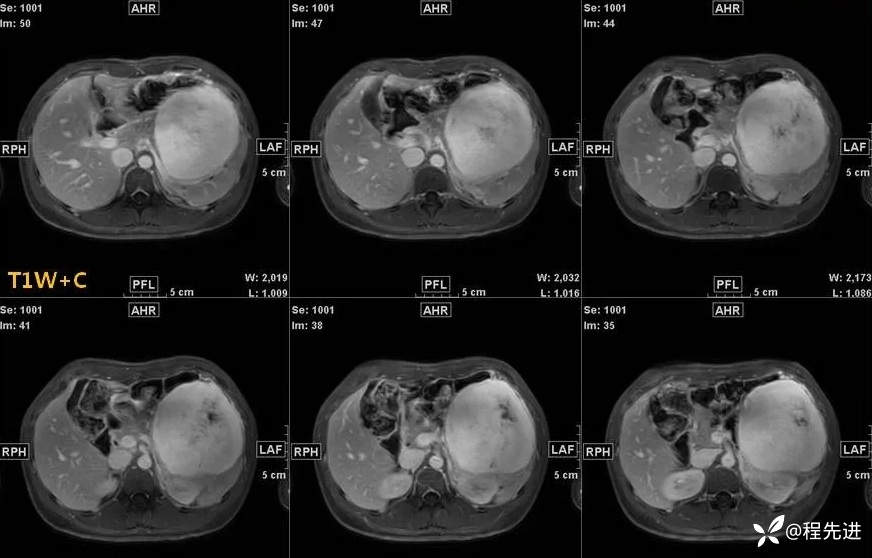

影像检查:

T1: